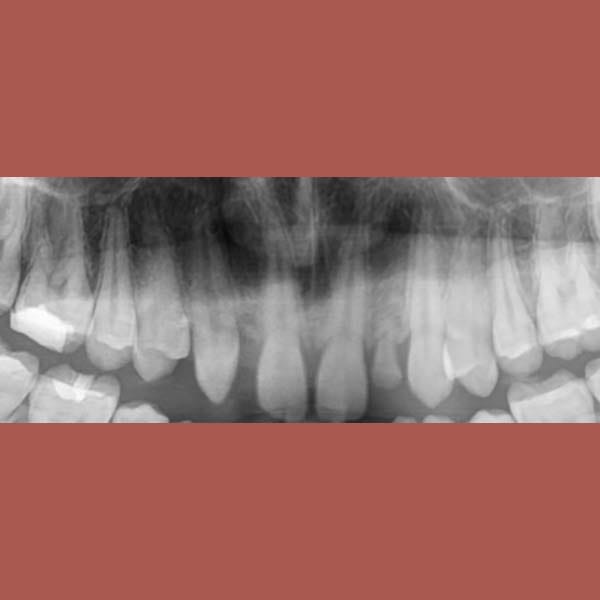

عانت هذه السيدة من وجود عضة عميقة أمامية و غياب خلقي لسنين أماميين سفليين ،بالإضافة لتراكب و عدم ارتصاف الأسنان الأمامية العلوية بشكل جيد – تم فتح مسافة كافية لوضع غرستين سنيتين و تم تصخيح العضة العميقة تقويمياً